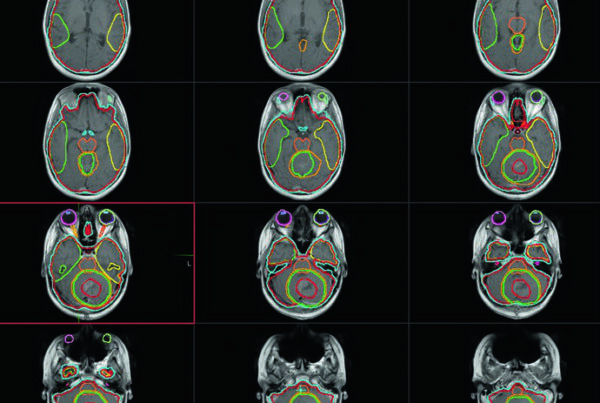

Uma das grandes virtudes do compêndio é sua abrangência. Para um mesmo sítio tumoral, as diretrizes oferecem restrições específicas para diferentes esquemas de fracionamento. Por exemplo, as recomendações para pulmão incluem tabelas separadas para regimes de 3, 4, 5, 8 e mais frações — eliminando a ambiguidade que ocorre quando se tenta interpolar restrições entre esquemas diferentes.

O documento inclui recomendações para sítios como cérebro, cabeça e pescoço, mama, pulmão, esôfago, estômago, pâncreas, fígado, reto, próstata, bexiga, ginecológico e coluna, entre outros. Essa abrangência é especialmente relevante para a prática diária de delineamento e setup em radioterapia, onde a padronização de restrições reduz variabilidade e melhora a consistência do cuidado.

A filosofia de documento vivo também se alinha com a prática de planejamento e delineamento em sarcomas e tumores cerebrais pediátricos, onde as restrições DVH precisam acompanhar a evolução das técnicas e da evidência clínica.